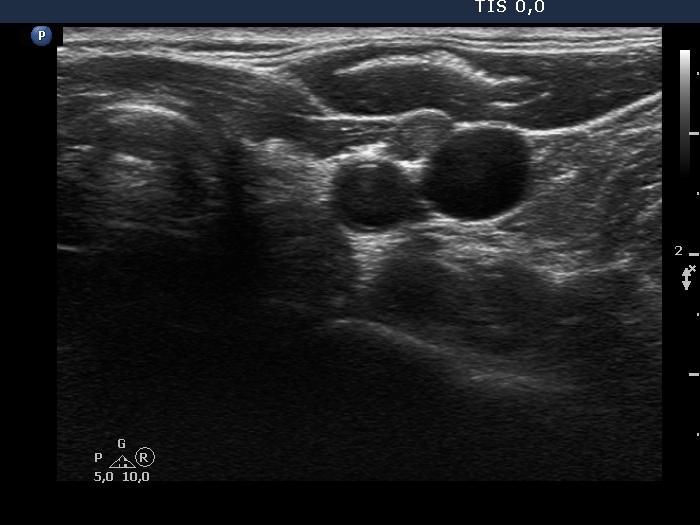

Follow-up investigation two years later (ultrasonographic picture 6)

Left lobe and lateral to the left lobe, transverse scan. There is a hypoechoic mas ventral and between the vessels.